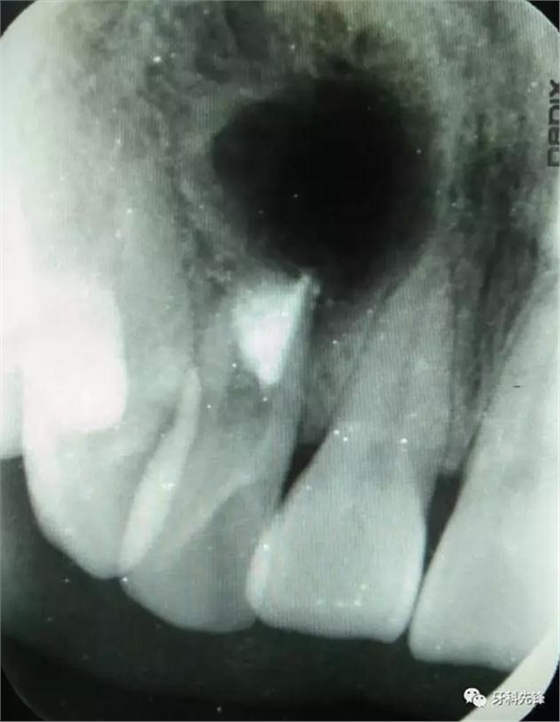

圖20.術(shù)后的根尖片影像檢查,根尖區(qū)MTA封閉完好。